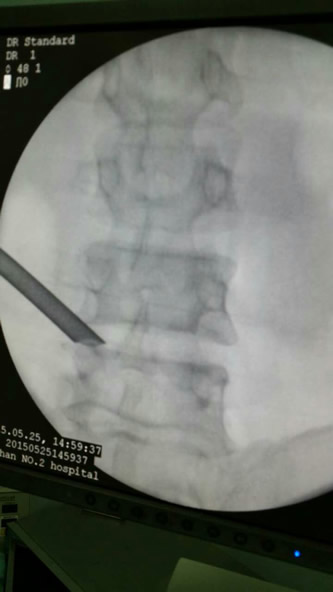

目前微创手术为脊柱外科的发展趋势,我院骨二科在魏人前主任带领下率先开展椎间孔内镜下腰椎间盘摘除术,通过靶点或精准穿刺到椎管。切口位于棘突旁开10-12cmm部位,切口大小1cm,用7.5mm管道经过椎间孔到达突出椎间盘处,插入内窥镜,在直视下行突出的髓核组织摘除,直接减压神经根,对椎管骚扰少。术后2小时后就可自行下床活动,一般住院2-3天出院。